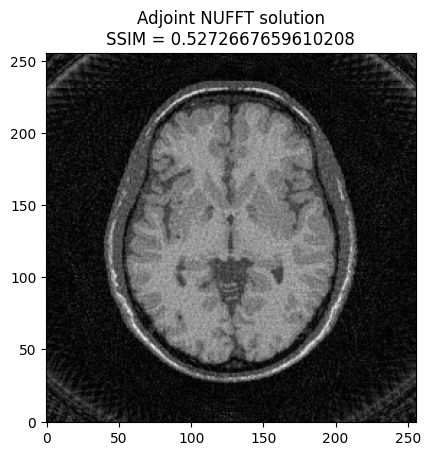

plt.imshow(np.abs(image2), cmap='gray')

# Calculate SSIM

base_ssim = ssim(image2, mri_img)

plt.title('Adjoint NUFFT solution\nSSIM = ' + str(base_ssim))